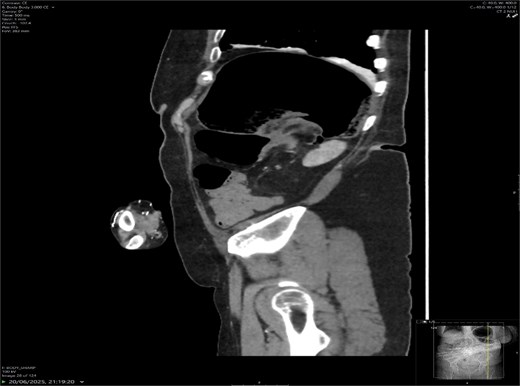

A contrast-enhanced CT scan of the abdomen demonstrated a whirl sign at the mesenteric root (Figs 1 and 2), dilated transverse colon with a transition point at the splenic flexure (Fig. 3), and no evidence of ischemia or perforation (Fig. 4). These findings were consistent with TCV.

Radiology plays a crucial role; plain abdominal radiographs may show nonspecific distension but rarely establish the diagnosis. A CT scan is the gold standard [8], with the whirl sign, transition point, and proximal dilatation being diagnostic. CT also assesses complications such as ischemia and perforation, which carry high mortality [9].